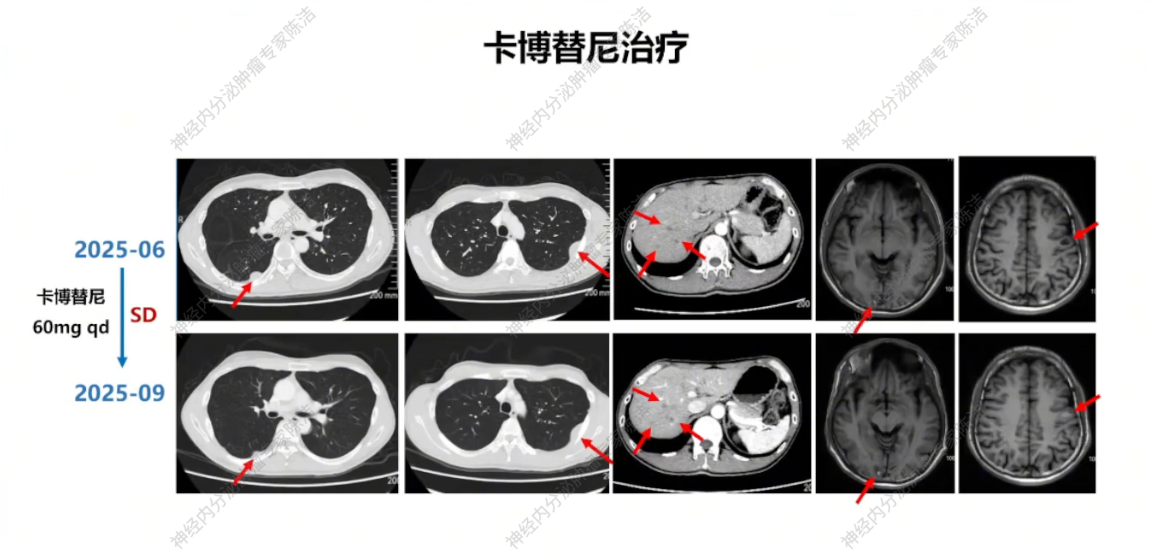

2025年7月23日,行左侧髂骨、坐骨、耻骨转移灶TOMO-IMRT 10次。考虑患者对伯瑞替尼耐药但MET扩增持续存在,2025年7月26日起改用多靶点药物卡博替尼,同时联合地舒单抗保骨治疗。2025年9月复查,影像学评估为SD,继续卡博替尼联合地舒单抗治疗。

放射诊断科汤伟教授:初诊胸部CT显示右下肺不规则结节,边缘有毛刺、高密度,影像学虽考虑恶性,但确诊需依赖病理。基线普美显MRI提示肝脏微小结节,当时判断转移可能性小,建议观察。CAPTEM方案治疗后,2023年7月右下肺及肝脏微小结节变化,疗效评估为PD。索凡替尼治疗后,右下肺及肝脏病灶继续增大,疗效评估PD。免疫/化免治疗期间,左肺上叶出现新转移灶及肝转移瘤增大,判定为PD。阿得贝利单抗维持期间为“进展的SD”,至11月明确PD。c-MET靶向治疗期,2024年12月至2025年3月伯瑞替尼治疗后取得PR,随后转为“增大的SD”,后更换为卡博替尼治疗,3个月后目前判定为SD。